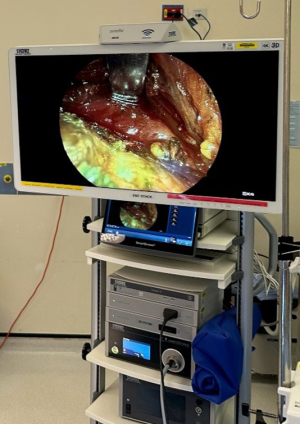

NIR was performed using the ICG rigid endoscope with Rubina camera head (Karl Storz, Tuttlingen, Germany). The endoscopic system utilizes a filter to switch between white light and NIR light emitted from a light-emitting diode (LED) source (Figures 1-3). The camera was used intermittently during key portions of the case to assist dissection and preservation of parathyroid tissue where in doubt, as well as for evaluation of the extracted thyroid specimen to identify any inadvertently removed parathyroid glands. Any identified glands were then reimplanted. The final specimen was then submitted to the same anatomical pathology laboratory for analysis.